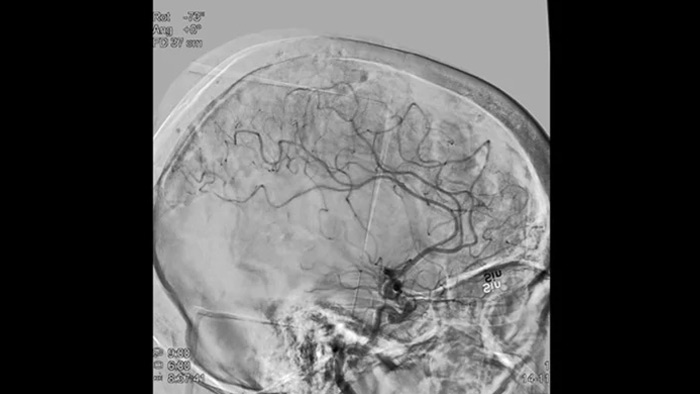

SmartCT Vaso IV

Compruebe la ubicación y la longitud de un coágulo

SmartCT Vaso permite la visualización más allá del coágulo con la adquisición de imágenes periprocedimiento de los aspectos del vaso distal en el accidente cerebrovascular isquémico. SmartCT Vaso es una técnica de adquisición basada en una exploración por TAC de haz cónico y una inyección de contraste intraarterial. Mediante la repleción retrógrada, las estructuras de los vasos antes y después del coágulo se vuelven visibles. Además, SmartCT Vaso 3D Roadmap puede utilizarse para visualizar dispositivos de recuperación de coágulos.